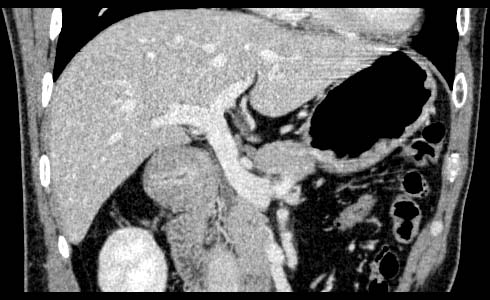

Gastric cancer / Borr.II

1mmx4, Pitch 4.5, 28 seconds, 150mAs

Coronal MPR

Data acquired & processed by R. Kato M.D.